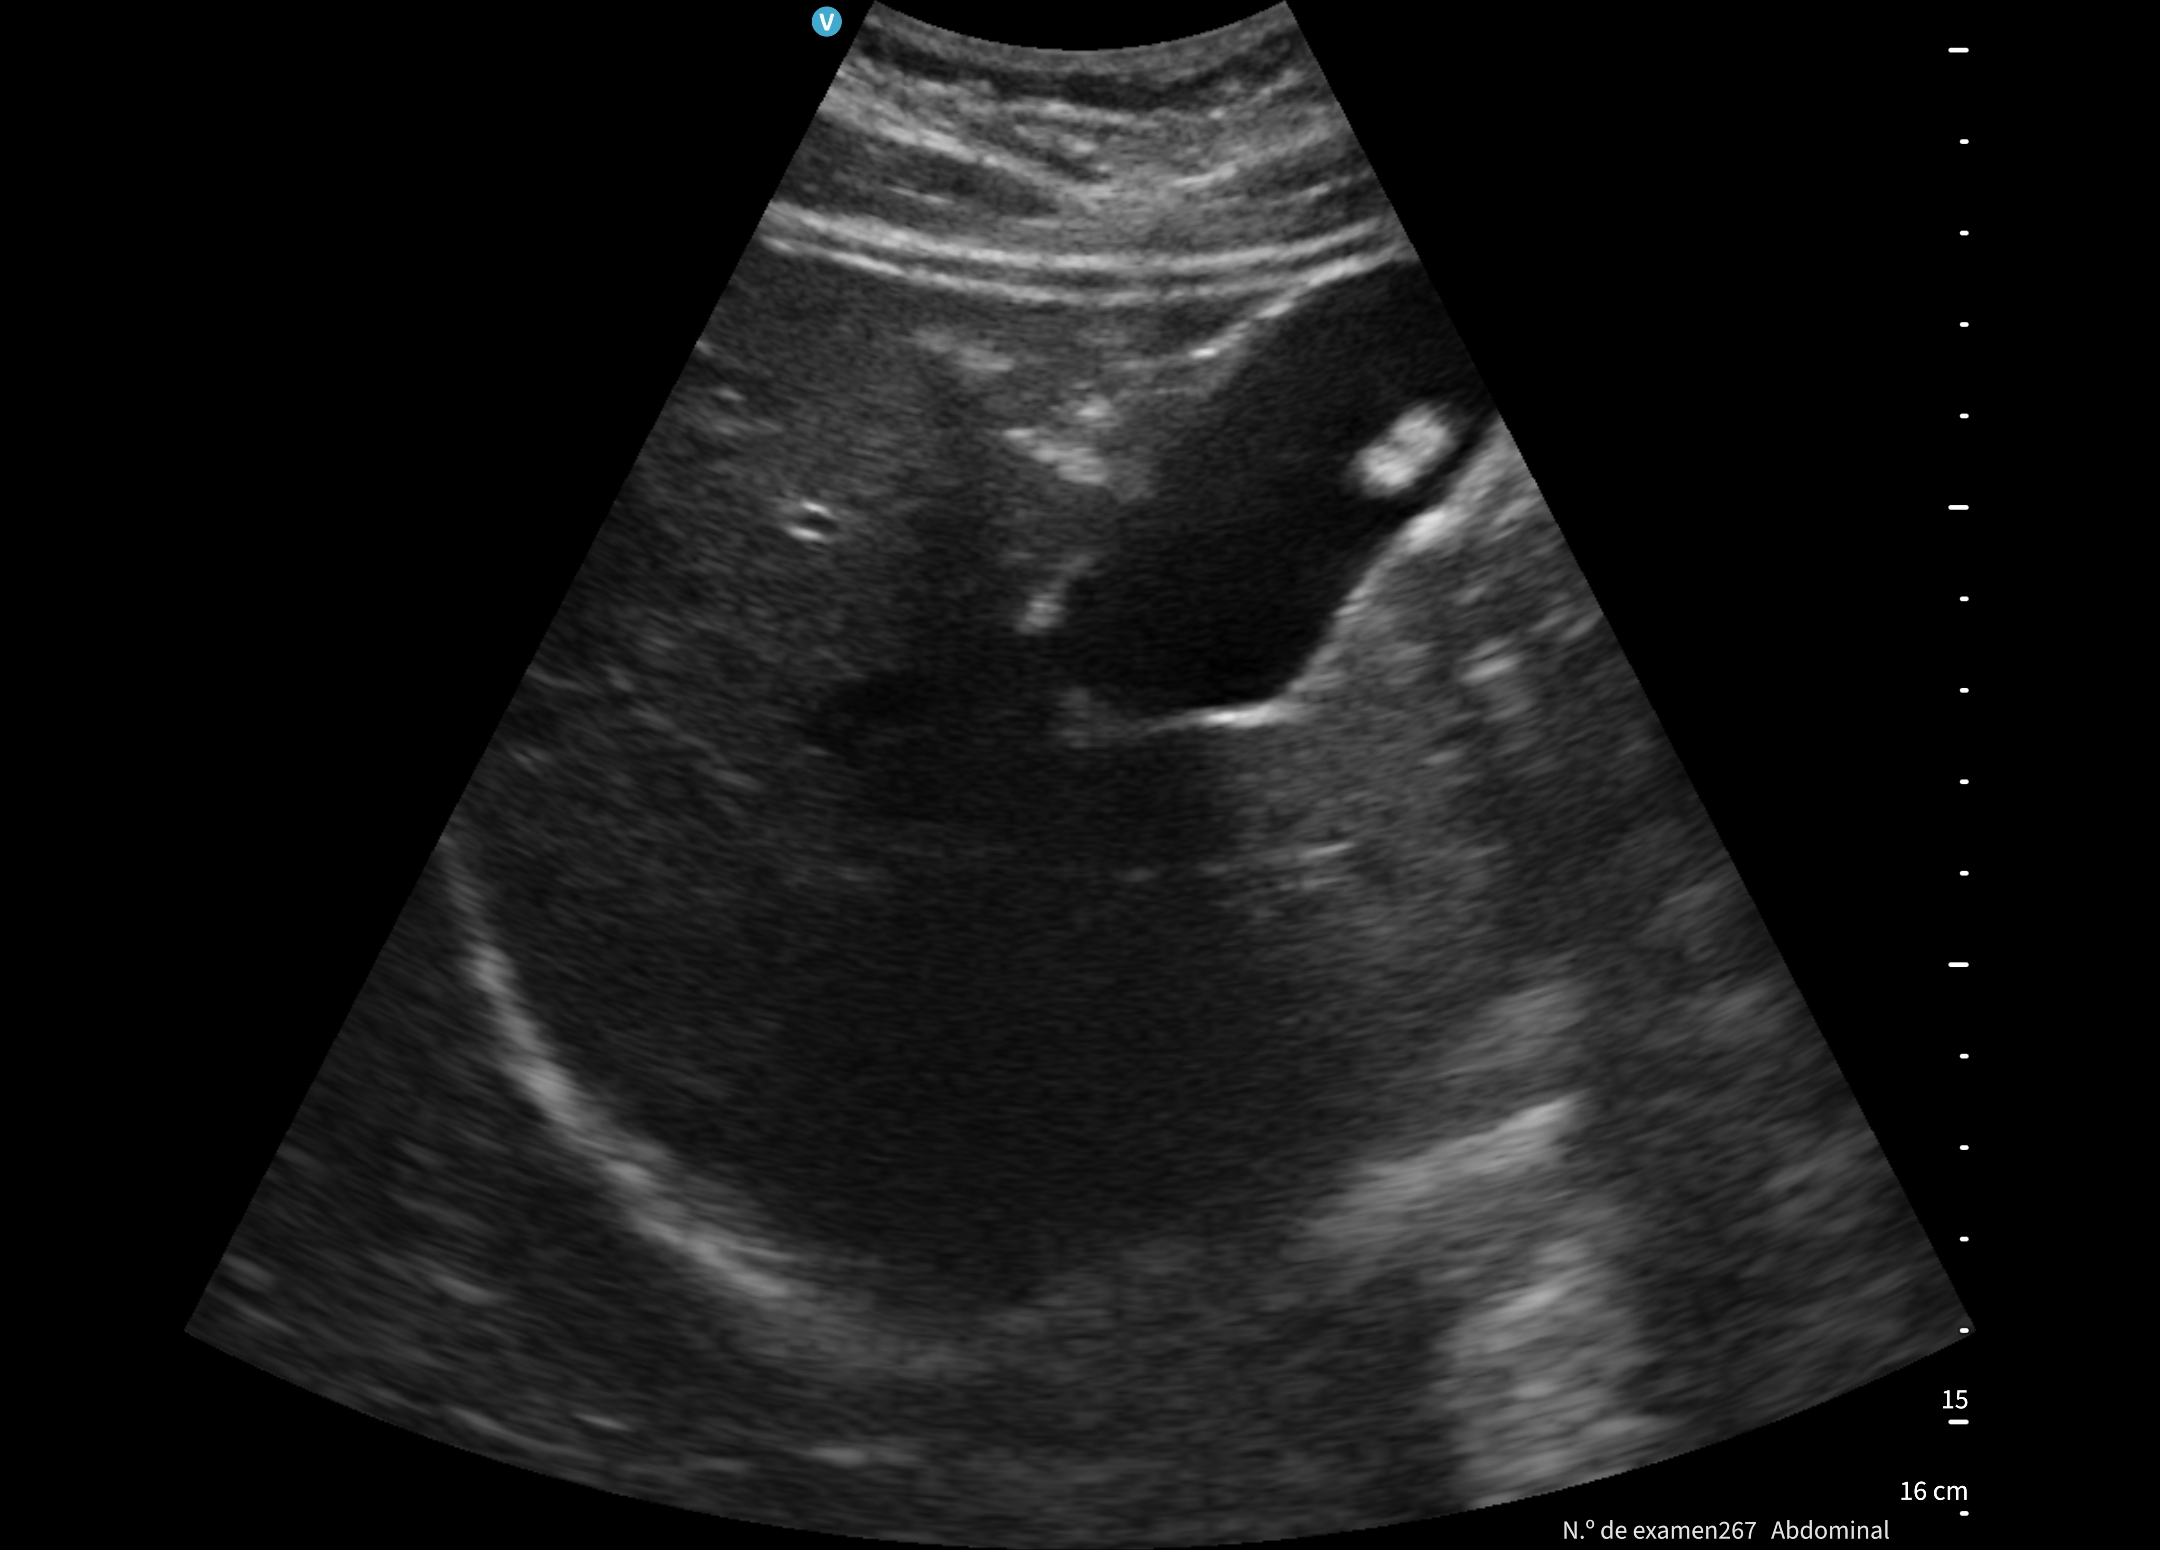

Se le cita en ayunas y realizamos una ecografía abdominal.

En la exploración abdominal se objetiva un cardias laxo de 2,19 cm, y la vesícula biliar distendida con colelitiasis múltiple.